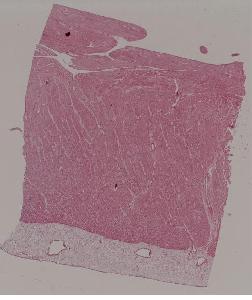

5.血管壁纤维样坏死